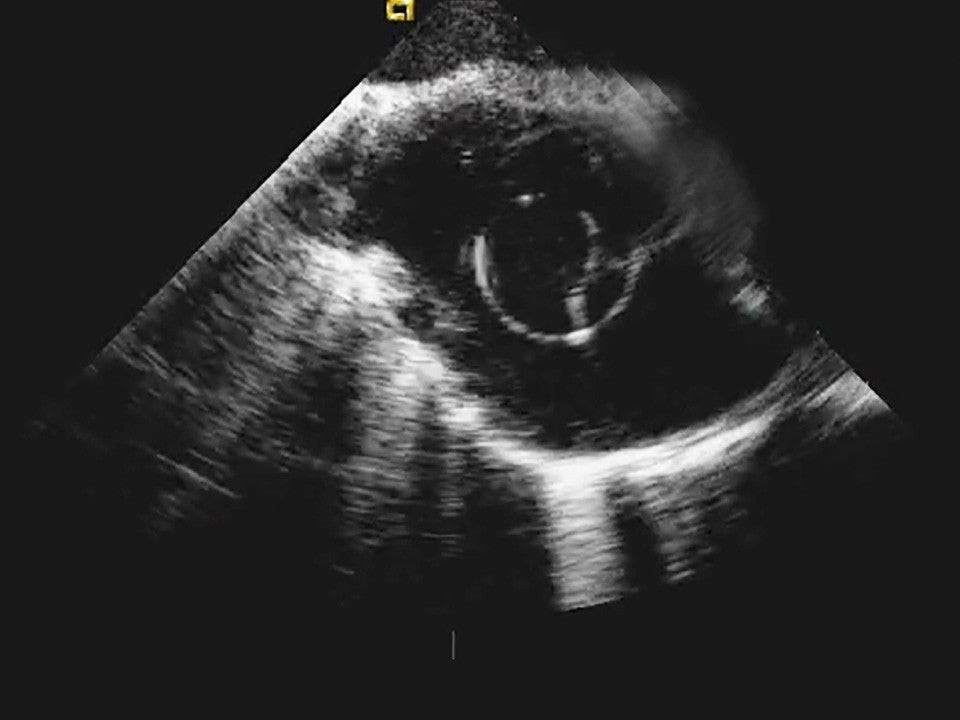

Image demonstrating that VersaCross Access Solution is echogenic.

Echogenic

Reliably locate your devices on ultrasound to reduce reliance on fluoroscopy